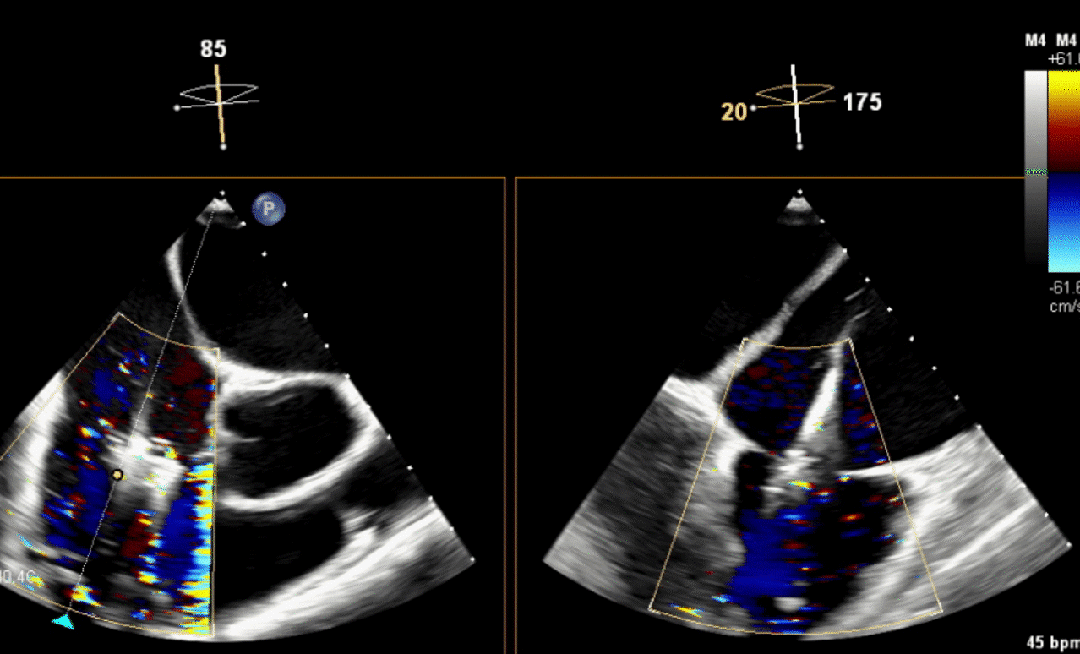

厦心成功完成机器人经导管二尖瓣微创手术

宁波市首两例经导管三尖瓣teer成功实施